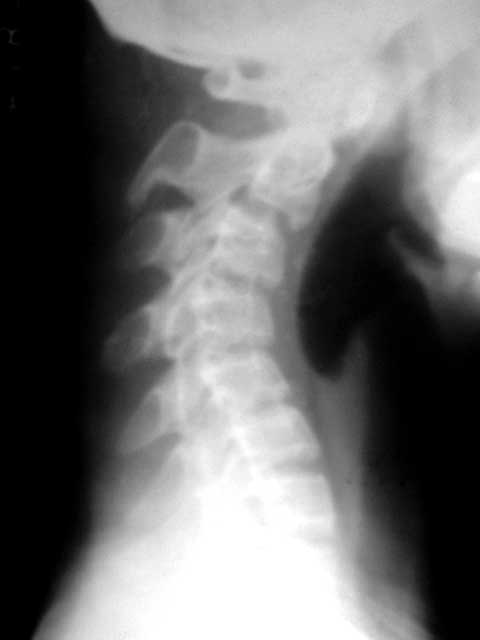

f/20y,在南方打工,电子车间作业,一坐就是五六个小时,现颈部痛。

很遗憾,只照了个侧位。

反屈如此厉害

那就是职业病引起的生理曲度消失

厉害!这么严重的颈椎反弓。[emb14]

颈椎极度后突畸形。难道每天坐五、六个小时就会出现这种改变吗?不知楼主是从哪里转贴过来的,最后的诊断是什么?

看侧位片下颌部下垂,肯定是头颈肌肉僵硬,病根还在颈部软组织。

颈椎反弓如此厉害,颈椎不稳,可怕!平常应该注意坐姿和锻炼身体。

我觉得这个病人不简单是职业病问题,5小时工作不至于此吧!不是我不同情劳动者,而是有蹊跷!首先肯定单个椎体形态还可以,可是测量好像有发育性椎管狭窄,即便如此也不至于此呀.另外只是颈痛是不存在手术干预条件的,希望患者改变习惯,更好维护自身健康!总觉得不对劲,吻合度差太多!

c23c34椎小关节不稳,需保护一下

这么严重的颈椎反弓

严重的颈椎反弓